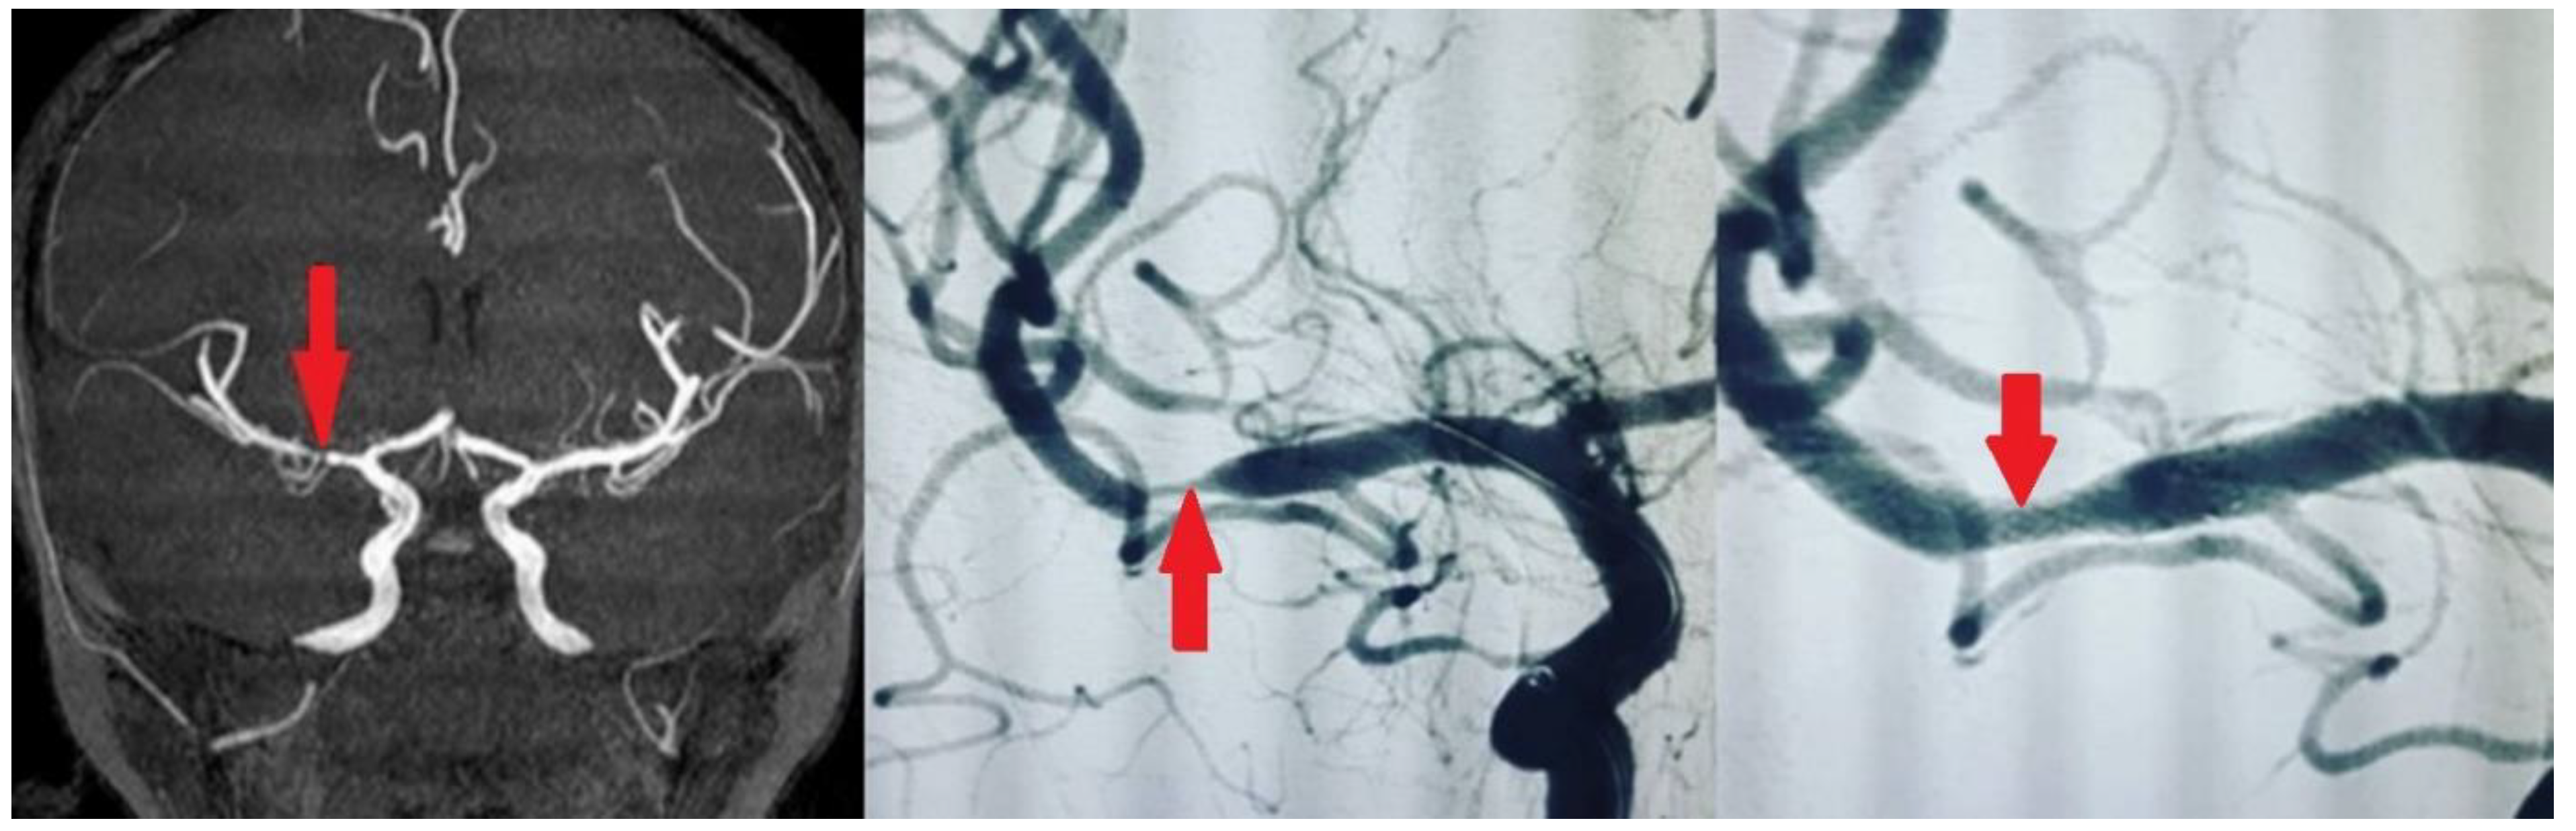

We used self-expanding stents (Enterprise® stent or ACCLINO® flex plus Stent). The responsible physician selected those stents, which were the best fit for each patient. Angiography was performed with an interventional system (Siemens Axiom Artis zee 2011; Siemens Healthcare, Erlangen, Germany), and predilatation with a balloon was performed in most patients. Examples of stenting in our patients are shown in Figure 1 and Figure 2. We used the Thrombolysis in Cerebral Infarction (TICI) scale to assess the degree of reperfusion following intracranial stenting. It classifies blood flow restoration into five categories based on angiographic findings. TICI 0 represents no perfusion, indicating complete occlusion with no distal flow. TICI 1 signifies minimal perfusion, where some contrast passes beyond the occlusion but without significant tissue perfusion. TICI 2a refers to less than 50% reperfusion of the affected vascular territory, whereas TICI 2b indicates more than 50% but incomplete reperfusion. The highest grade, TICI 3, reflects full perfusion, where the treated vessel achieves complete restoration of blood flow. We accepted TICI 2b–3 as successful revascularization, as it correlates with better functional outcomes and reduced long-term disability.

Figure 2. Symptomatic atherosclerotic stenosis in the middle cerebral artery M1 branch in a 57-year-old male patient, with a history of type 2 diabetes mellitus and hyperlipidemia, was treated with elective intracranial stenting.